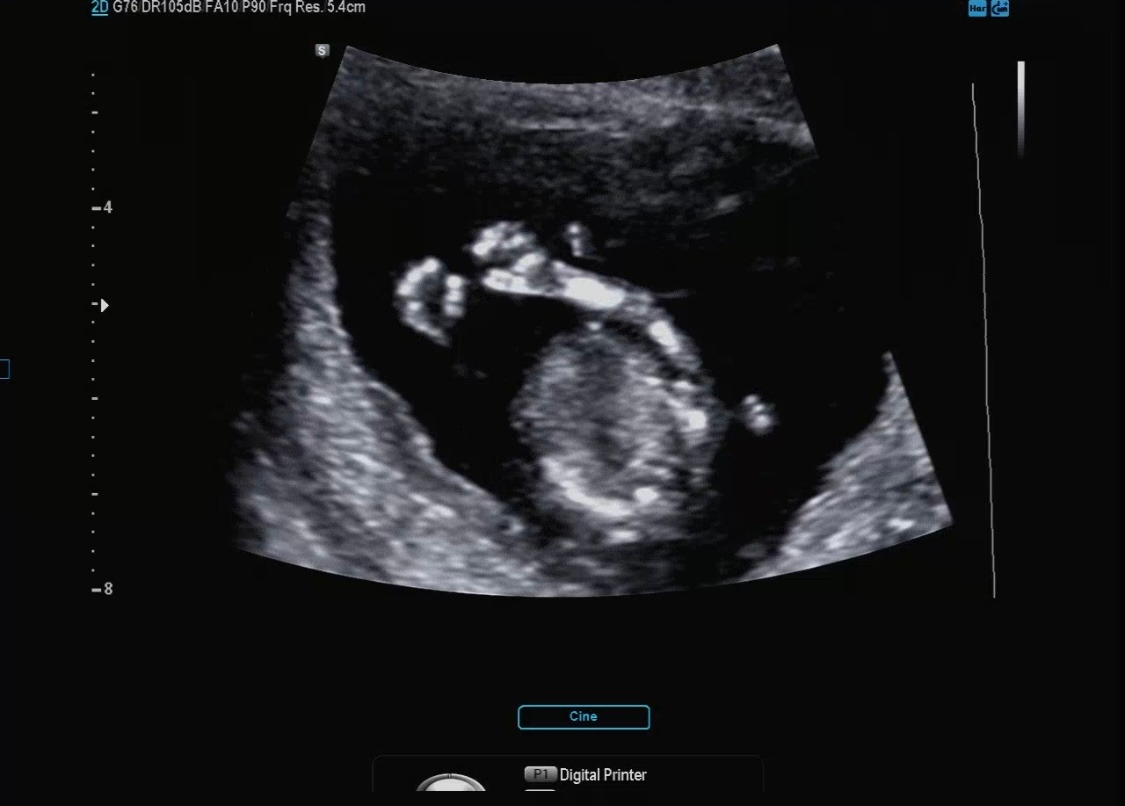

그나마 가랑이 사이를 보여 준 영상을 캡처 한 부분이다. 잘 안 보이는데 밋밋해 보여서 여아 같지만 뭔가 또 보이는 것 같기도 하고....ㅎㅎ 다올이는 남자일까 여자일까?

12주 각도 법에 의하면 옆으로 누워있는 사진을 봤을 때 남아는 약간 위쪽 각도로 생식기가 보이고 여아는 수평하게 일자로 생식기가 보인다고 하더라 (ㅎㅎㅎ) 정확한 건 아니다. 성별이 궁금한 엄빠들의 부단한 노력의 결과..

각도 법을 봐도 뭔가 딸아이 같다. 근데 태몽은 남아였는데...(?!) 남자 아이던 여자 아이던 나는 둘 다 좋지만 그냥 궁금하다. 성별이 ㅎㅎ 그리고 남아면 힘들다고 주변에서 하도 그래서 체력을 키우고 마음의 준비를 해야 할 것 같다.